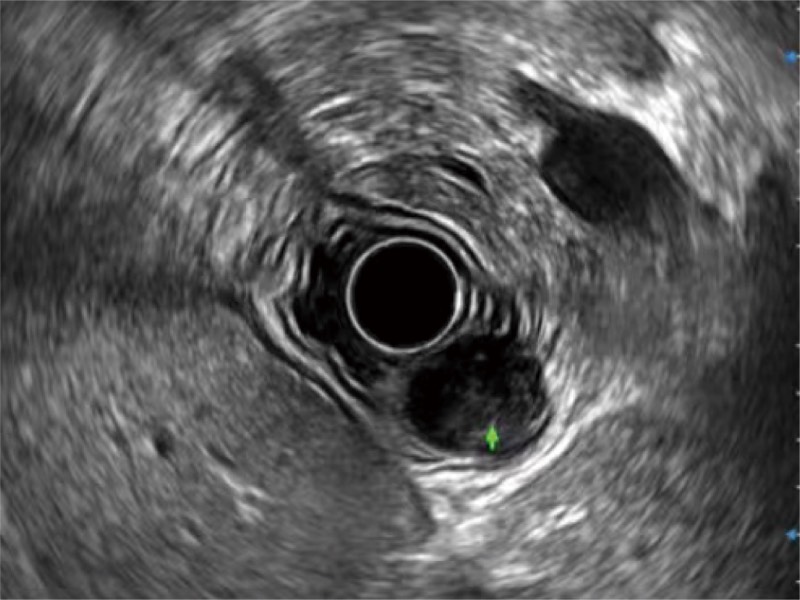

食管內(nèi)間質(zhì)瘤清晰顯像